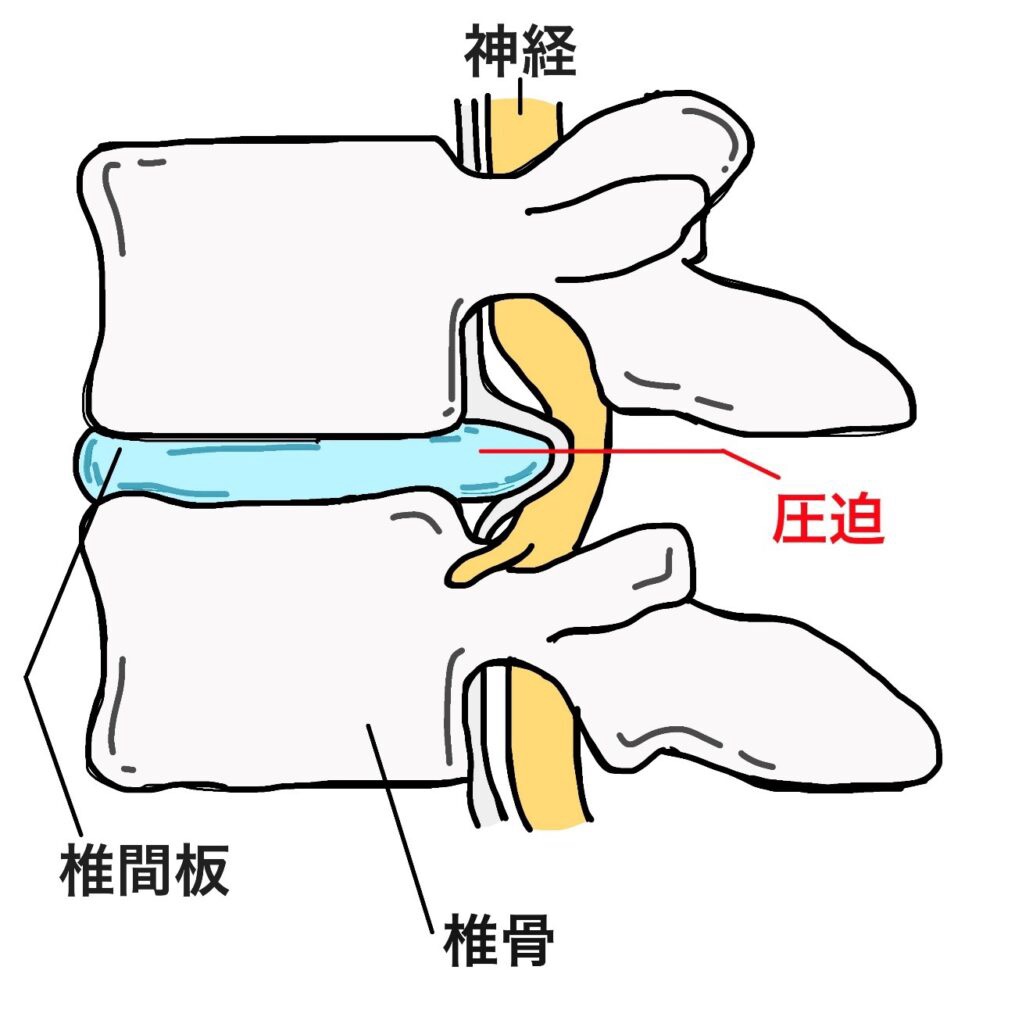

首の骨(頸椎)の間にあるクッション「椎間板」が飛び出し、神経を圧迫してしまう状態を頸椎椎間板ヘルニアといいます。

首ヘルニアを放っておくと、神経の圧迫が進み、痛みやしびれが長引くケースもあります。